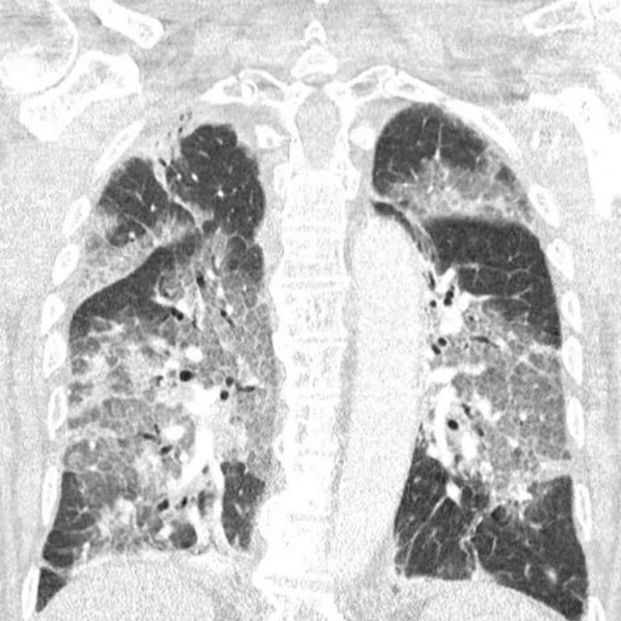

A raíz de este suceso, los sanitarios neerlandeses han escrito una carta al ministro de Sanidad, Hugo de Jonge, en la que critican la actitud del gobierno al paralizar la vacuna de Janssen y las limitaciones de edad impuestas al uso de la vacuna de AstraZeneca. Acompañaron la carta con una radiografía de los dañados pulmones del paciente, una imagen que se ha vuelto viral en redes sociales.

"Hoy ingresó en nuestro hospital el primer paciente que se había negado a recibir la vacuna de AstraZeneca tras toda la conmoción en la prensa. Oímos el tremendo pesar en su voz y la desesperación en sus ojos. El virus lo ha atacado y podría haberse evitado. Con su permiso, compartimos su escáner de pulmón. No es necesario ser un especialista en pulmones para reconocer la devastación, ni epidemiólogo para explicar los riesgos de no estar vacunado", advertían.